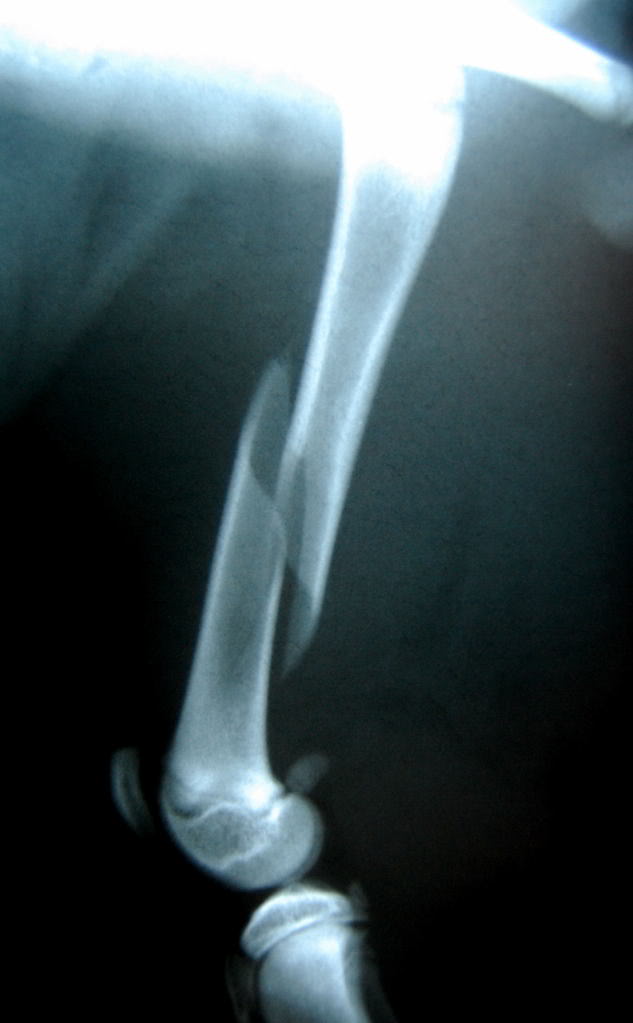

Femur fracture (mid-shaft oblique) repair with IM pins and cerclage wire. The cause of the fracture is unknown but no other injuries sustained.